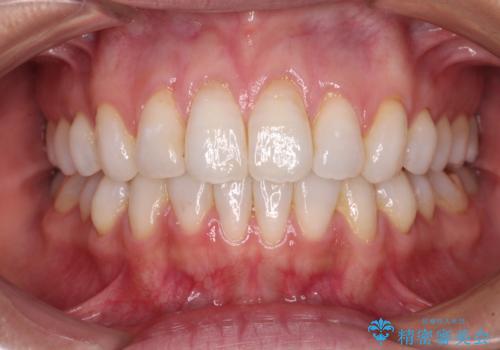

- 八重歯を気にして来院された高校生の患者様です。

ボディーコンタクトの激しい部活動を行っているため、補助装置とインビザラインを用いて、部活動を継続しながら治療を行うこととしました。

八重歯を効率よく改善するため、補助装置を使用して上顎の奥歯を後方に移動させました。

部活動をしながらでしたが、マウスピースをしっかりと装着してくださったので、1年半程度で終了することができました。